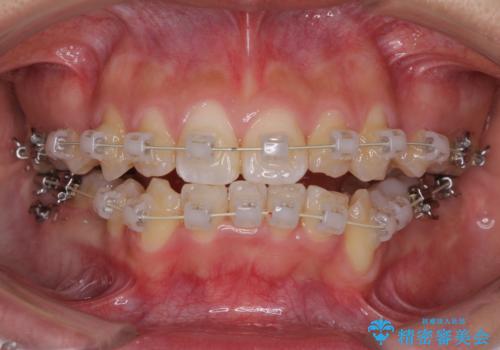

前歯が八重歯でガタガタ ワイヤーによる抜歯矯正

- 前歯のガタガタを主訴に来院されました。

前歯の重度のガタガタで、八重歯もある状態でした。

また右下の乳歯が残っており、永久歯が1本足りませんでした。

上顎両側と左下の前から4番目の歯と、右下の乳歯を抜歯して矯正することとなりました。

乳歯を抜歯することにより、通常よりは治療期間を要してしまいましが、前歯のガタガタもなくなりきれいな歯並びになったと喜んでいただけました。